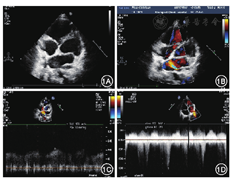

体格检查:口唇轻度紫绀,无杵状指,皮肤黏膜未见出血点。两肺呼吸音清,对称,未及啰音。心律齐,心前区未及杂音。6 min步行距离350 m,步行后经皮血氧饱和度(SaO2)降低至63%。实验室检查:血红蛋白120 g/L,血浆N末端B型利钠肽原(NT-proBNP)132 pmol/L。动脉血气:pH值7.38,SaO2 92%,氧分压68 mmHg(1 mmHg=0.133 kPa),二氧化碳分压38 mmHg。超声心动图:心内结构正常,左肺静脉入左心房口处狭窄,内径5 mm,彩色多普勒提示该处流速增快,峰值1.9 m/s;据三尖瓣反流束估测肺动脉收缩压42 mmHg(图1);右心声学造影阴性。腹部B超:肝脾位置形态正常。肺血管增强CT:主肺动脉及各叶段肺动脉分支显影好;左侧肺动脉明显稀疏,左上、下肺静脉汇合一共同静脉干开口于左心房后壁,伴入口处狭窄;右下肺静脉近端迂曲呈瘤样扩张,与右上肺静脉共汇开口至左心房。